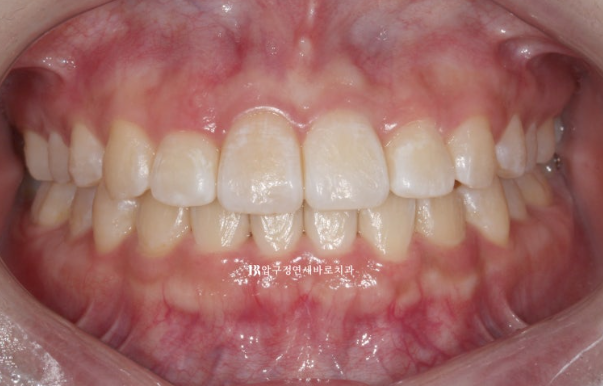

3개월에 걸쳐 14개의 첫 세트 치료를 마무리 한 후 모습입니다.

앞니 뻗침이 많이 개선이 되었지만 앞니를 조금 뒤로 더 넣고 싶다 라는 환자분의 요구에 부응하여 추가장치 제작에 들어갔습니다.

23.08

웃을 때 치아가 일자로 딱 떨어지는 모양새가 보기 좋습니다.